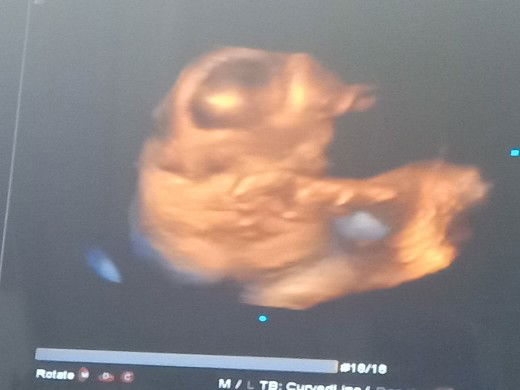

hpl

Bulan kemarin Usg katanya hpl 3januari... Bulan ini usg malah mundur jauh hpl tanggal 20januari... Emang gitu yahh bun tiap bulan hpl pasti berubah2 ... Usg 4D 32week...